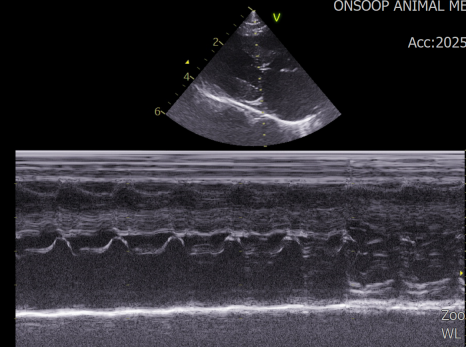

심장초음파 검사 결과 / 출처: 24시온숲동물의료센터

심장 초음파 검사: HCM(비대성 심근병증) 과 SAM(승모판연관 이첨판전방이동) 소견이 확인되었습니다.